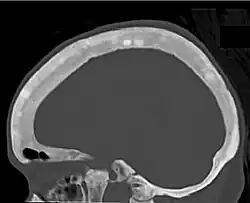

Renal osteodystrophy is usually diagnosed after treatment for end-stage kidney disease begins; however the CKD-MBD starts early in the course of CKD.[1][6] In advanced stages, blood tests will indicate decreased calcium and calcitriol (vitamin D) and increased phosphate, and parathyroid hormone levels. In earlier stages, serum calcium, phosphate levels are normal at the expense of high parathyroid hormone and fibroblast growth factor-23 levels. X-rays will also show bone features of renal osteodystrophy (subperiostic bone resorption, chondrocalcinosis at the knees and pubic symphysis, osteopenia and bone fractures) but may be difficult to differentiate from other conditions. Since the diagnosis of these bone abnormalities cannot be obtained correctly by clinical, biochemical, and imaging methods (including measurement of bone-mineral density), bone biopsy has been, and still remains, the gold standard analysis for assessing the exact type of renal osteodystrophy.[6][16]